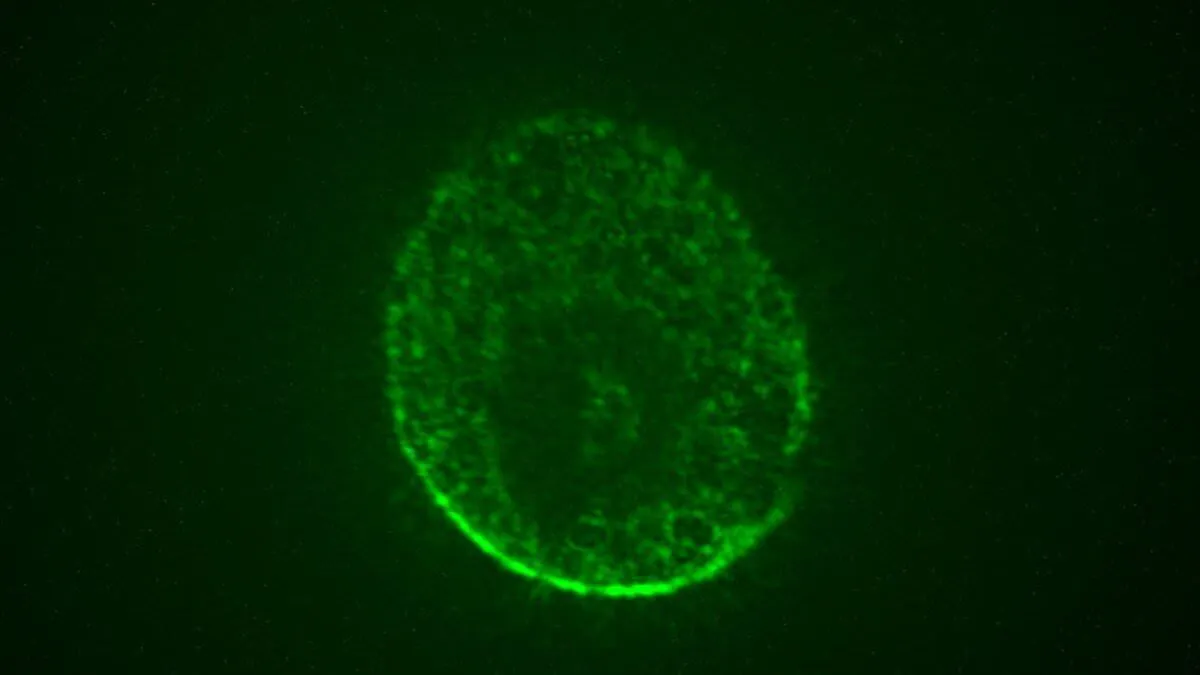

آنها یک پروتئین ژن فلورسنت را روی ناقل ویروسی سوار کردند. اگر این ماده به طور موفقیت آمیز از نورونها میگذشت و ژن را داخل آنها میکاست، ناقلان ویروسی با رنگ سبز نئونی میدرخشیدند.

سلولها طی ۷۲ ساعت نه تنها خود را به شکل ارگانوئیدهای ۳ بعدی مغز انسان سازماندهی کردند، بلکه میدرخشیدند. اما مهمتر آن محققان هنگام بررسی میکروسکوپی شاهد یک توده بافت سبز رنگ درخشان بودند.